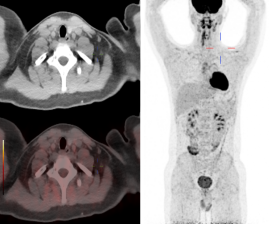

患者A未进行保暖PET/CT图像

患者A进行保暖后复查PET/CT图像